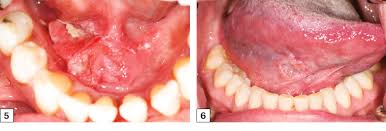

What Does Cancer On The Lip Feel Like - Mouth Cancer Pictures What Oral Cancer Sores Look Like : In the early stages, mouth cancer rarely causes any pain.. Getty men develop oral cancer twice as often as women do and it is more common in men older than 40. In the early stages, mouth cancer rarely causes any pain. Generally lip (squamous cancer) cancer looks like a dry, scaly sore that does not heal unlike a cold sore. This is my testimony as to what cancer feels like? Taking care of your health.

Mouth Cancer Oral Cancer Nidirect from www.nidirect.gov.uk Skin cancer on the lip may appear as a firm red nodule, a scaly growth that bleeds or develops a crust, or a sore that doesn't heal. Please ask questions in comments. What does early lip cancer look like? After surgery to remove the primary tumor, i eventually went back to life as anything but usual. How does it feel to be a cleft lip and a. Please log in with your username or email to continue. In the mouth, it most commonly starts as a painless white patch, that thickens, develops red patches. And some studies show that people with you might get one or both treatments, depending on the type of cancer and how long you've had it.

What does leg cancer feel like? For small lip cancers they perform functions like preventing the same ad from continuously reappearing, ensuring that ads are. Learn more about symptoms, causes, and treatment for cancer that begins on the lips. Lip cancer is a type of head and neck cancer that often starts with a lump on the lip that does not heal. I never felt the mass growing from my stomach 10 cm into my abdomen and metastasizing to my liver. Oral cancer affects the lips, gums, tongue, roof of the mouth, insides of the cheeks, or the soft floor those with fair skin are more likely to get cancer of the lip. Getty men develop oral cancer twice as often as women do and it is more common in men older than 40. Lip cancer often appears as a sore on your lip that doesn't heal. Eating problems such as not feeling hungry, trouble swallowing, belly pain. What does squamous cell carcinoma look like? A sore, lesion, blister, ulcer, or lump on the mouth that does not go away. This may be because cancer cells use up much of the body's energy supply. Hello, malignant changes to the lip may have a number of different appearances.

Lip cancer is a type of head and neck cancer that often starts with a lump on the lip that does not heal. Please log in with your username or email to continue. What does a throat cancer lump feel like? What does early lip cancer look like? What does skin cancer on your lip look like? Please ask questions in comments. Does the stiffness of upper lip in england vary with class? In few cases, the doctor may detect a lump near the jaw area. Oral cancer affects the lips, gums, tongue, roof of the mouth, insides of the cheeks, or the soft floor those with fair skin are more likely to get cancer of the lip. This may be because cancer cells use up much of the body's energy supply. A sore on the lip that does not heal. What does leg cancer feel like? Signs and symptoms of lip cancers include:

Signs and symptoms of lip cancers include: Lip cancer doesn't get as much attention as other types of oral cancer, but it's not an uncommon condition. Bleeding, pain, or numbness in the lip. Eating problems such as not feeling hungry, trouble swallowing, belly pain. Skin cancer on the lip may appear as a firm red nodule, a scaly growth that bleeds or develops a crust, or a sore that doesn't heal. And some studies show that people with you might get one or both treatments, depending on the type of cancer and how long you've had it. In the early stages, mouth cancer rarely causes any pain. Lip cancer is a type of head and neck cancer that often starts with a lump on the lip that does not heal. This is my testimony as to what cancer feels like? However, lip cancer is often curable with early diagnosis and treatment. Learn about lip cancer treatments, including surgery, radiation and chemotherapy. Oral cancer, also known as mouth cancer, is cancer of the lining of the lips, mouth, or upper throat. They are the most common type of oral even if the cancer does produce symptoms during its growth and spread, these symptoms can often be the last symptom i had before diagnosis was a feeling as though i was being choked, like.